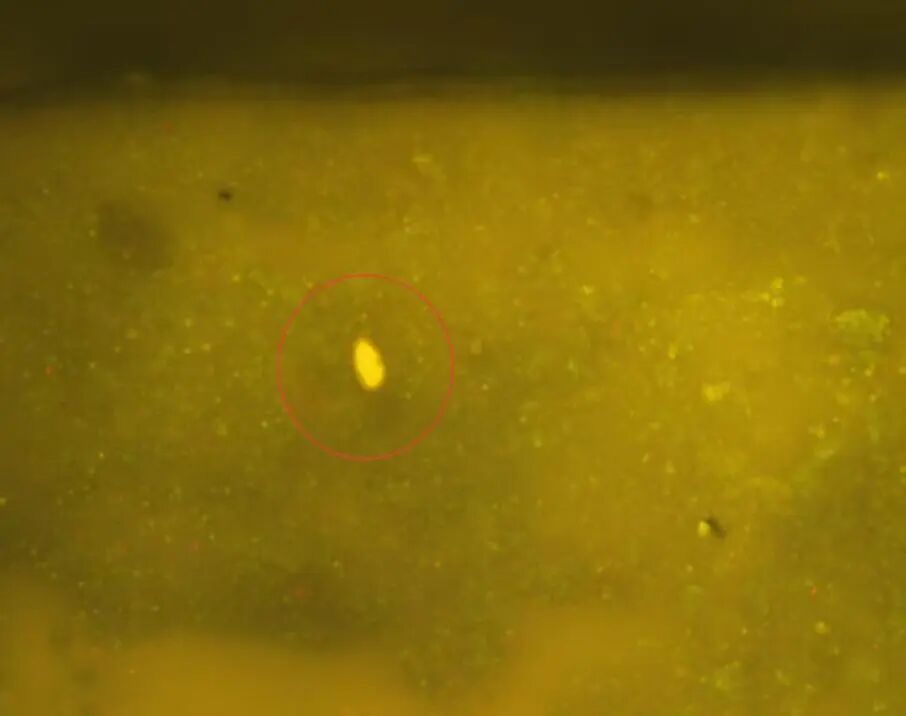

显微镜下观察到的肝吸虫卵